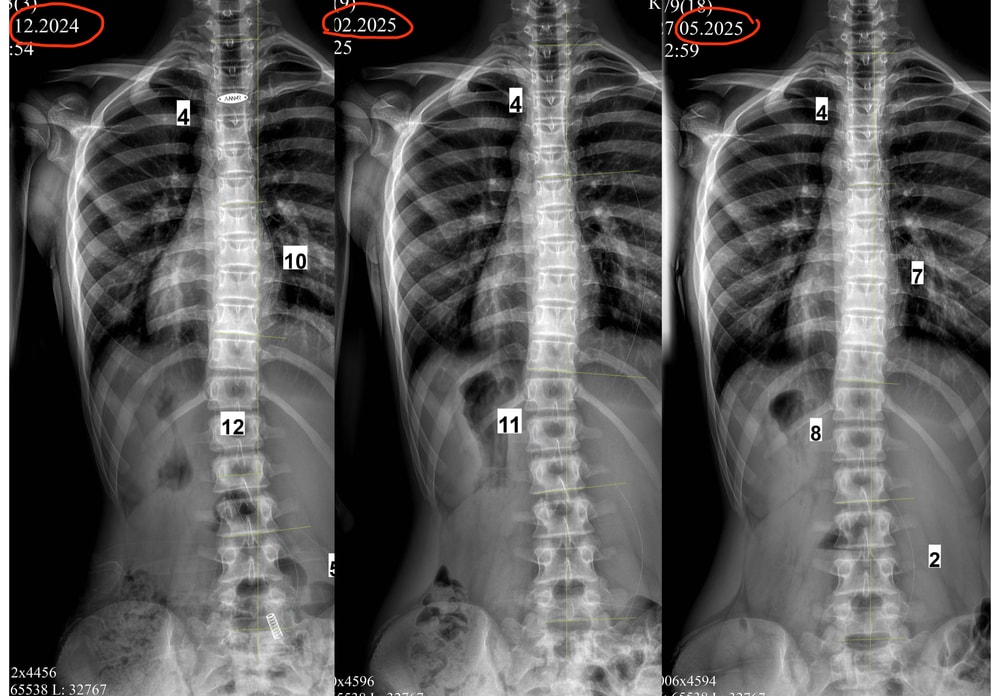

Апдейт от декабря 2024:

Фото без корсета перед выдачей прошлого корсета ( декабрь 2023), и фото без корсета перед заказом нового ( декабрь 2024). Выросла, 177 см,поэтому опять замена (

В декабре 2024 (6,5 лет в корсете, взраст 13 лет 9 мес) нам сказали что делать новый все таки не будут, градусы маленькие, вдруг гиперкоррекция случится) очень было тревожно, но корсет сняли, через три месяца рентген-осмотр 25.02.2025 - пока все ок, еще три месяца гуляем без корсета. Будем делать рентген каждые три месяца, так сейчас самый опасный момент - М нет, рост идет, за три месяца добавила 1 см, итого 177,5 см, через 5 дней 14 лет.

Обновление от мая 2025, рост 179,5(+2см за 3 мес)

Без корсета 6 мес. По снимкам даже улучшение, если это не погрешность, то я в шоке.